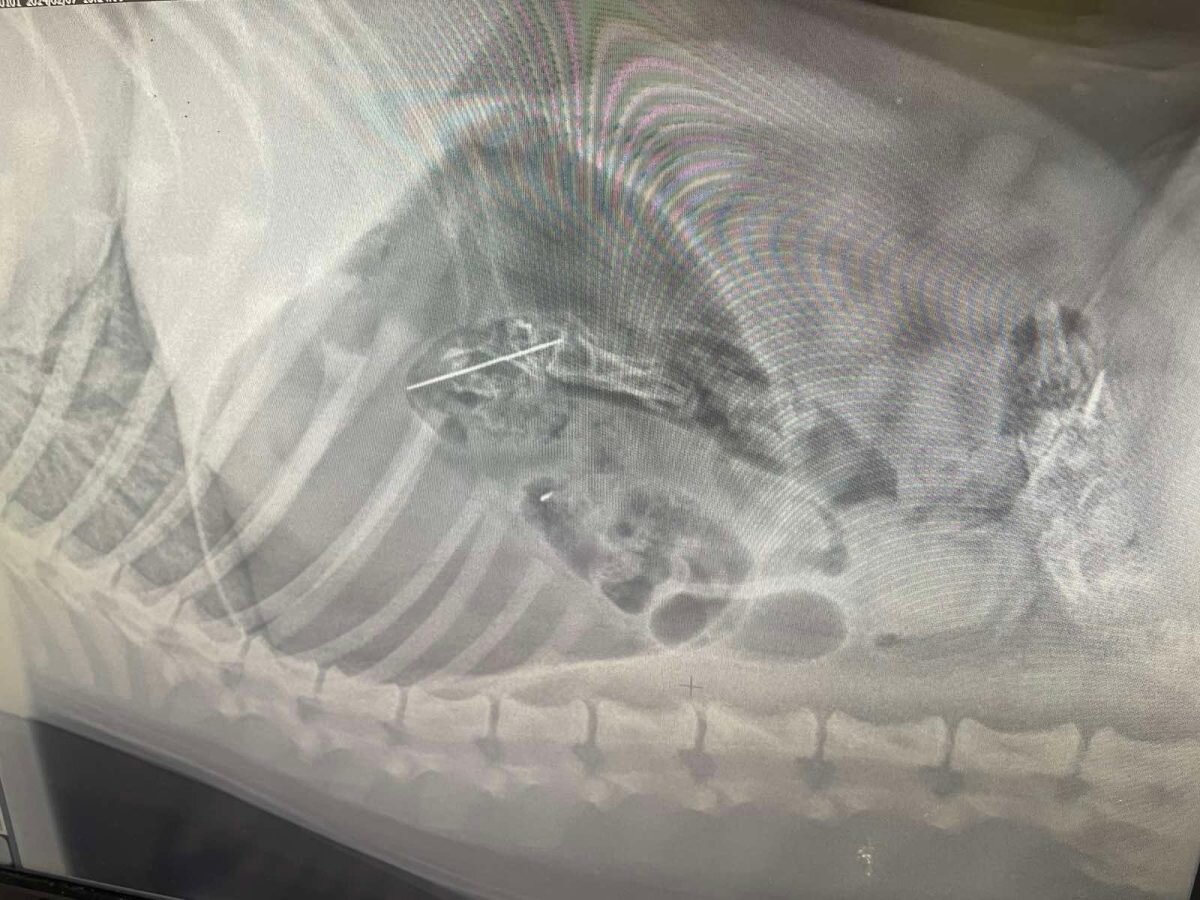

Ветеринар спас проглотившего иголку 6-месячного лабрадора в Канавинском районе Нижнего Новгорода, сообщается в соцсетях местного госветуправления. Инцидент произошел вчера, 26 февраля. Хозяйка щенка вовремя не убрала иголку со стола. Через минуту лабрадор уже проглотил опасный предмет: в силу возраста пушистик грызет все, что ему попадается. Питомца сразу же привели к ветеринару. Тем не менее, игла уже ушла дальше двенадцатиперстной кишки, поэтому достать ее при помощи эндоскопа уже было невозможно. В итоге лабрадору сделали полостную операцию. Иглу с ниткой извлекли из тонкого отдела кишечника. Сейчас пушистик чувствует себя удовлетворительно. Ранее на сайте pravda-nn.ru сообщалось о том, что волонтеры спасают попавшую в отлов собаку с травмой лапы в Нижнем Новгороде. Фото: Госветуправление Нижнего Новгорода ВКонтакте Фото: Госветуправление Нижнего Новгорода ВКонтакте Ещё новости по теме Бездомный пес самостоятельно пришел в приют в Нижнем Новгороде Ветврачи спасли чихуахуа, которого

Питомца сразу же привели к ветеринару. Тем не менее, игла уже ушла дальше двенадцатиперстной кишки, поэтому достать ее при помощи эндоскопа уже было невозможно.

В итоге лабрадору сделали полостную операцию. Иглу с ниткой извлекли из тонкого отдела кишечника. Сейчас пушистик чувствует себя удовлетворительно.